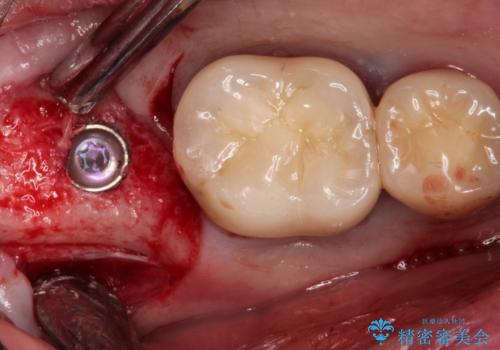

インプラントを入れるためには十分な骨の高さと幅が必要です。術前に検査を行い必要であれば別途、骨や角化歯肉を増やす治療も行う事があります。

インプラントの土台と被せ物は適合が良い物を制作するため、シリコン印象材を使用し型を取っています。